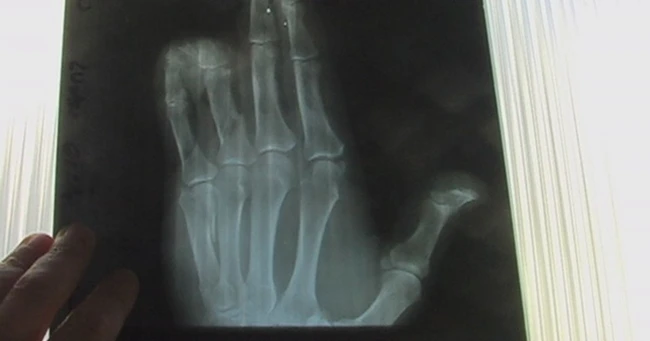

Radiografie

„După acordarea primelor îngrijiri medicale, pacientul a fost du în sala de operaţii a Clinicii de Chirurgie Reconstructivă.Pronosticul este rezervat din cauza leziunilor complexe cu amputatii traumatice de degete şi multiple fracturi", a explicat medicul Tudor Ciuhodaru de la Spitalul de Urgenţe „Sfântul Ioan".